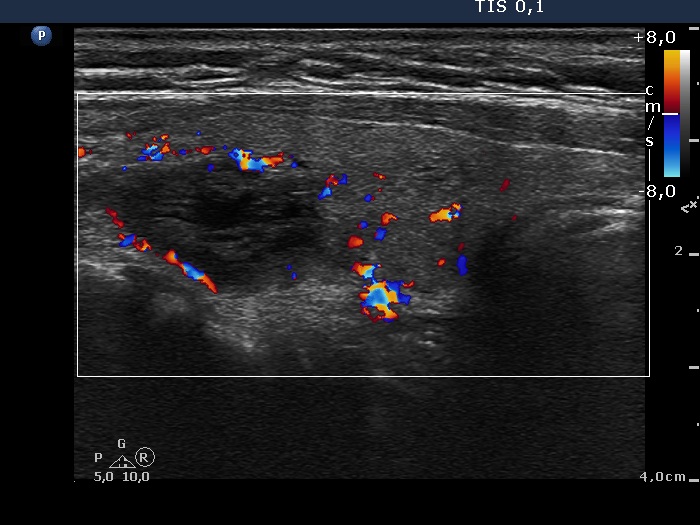

Ultrasonography. The thyroid was echonormal. There was large cyst in the right lobe. The cyst seemed to be a peripheral-type lesion with an inhomogeneous solid part having numerous hyperechogenic figures which belonged to the non-specific category. There were two hyperechogenic lesions in the right while a moderately hypoechogenic one in the left lobe.

After aspirating 9 mL troubled fluid it became evident that the cyst indeed is a central-type lesion.